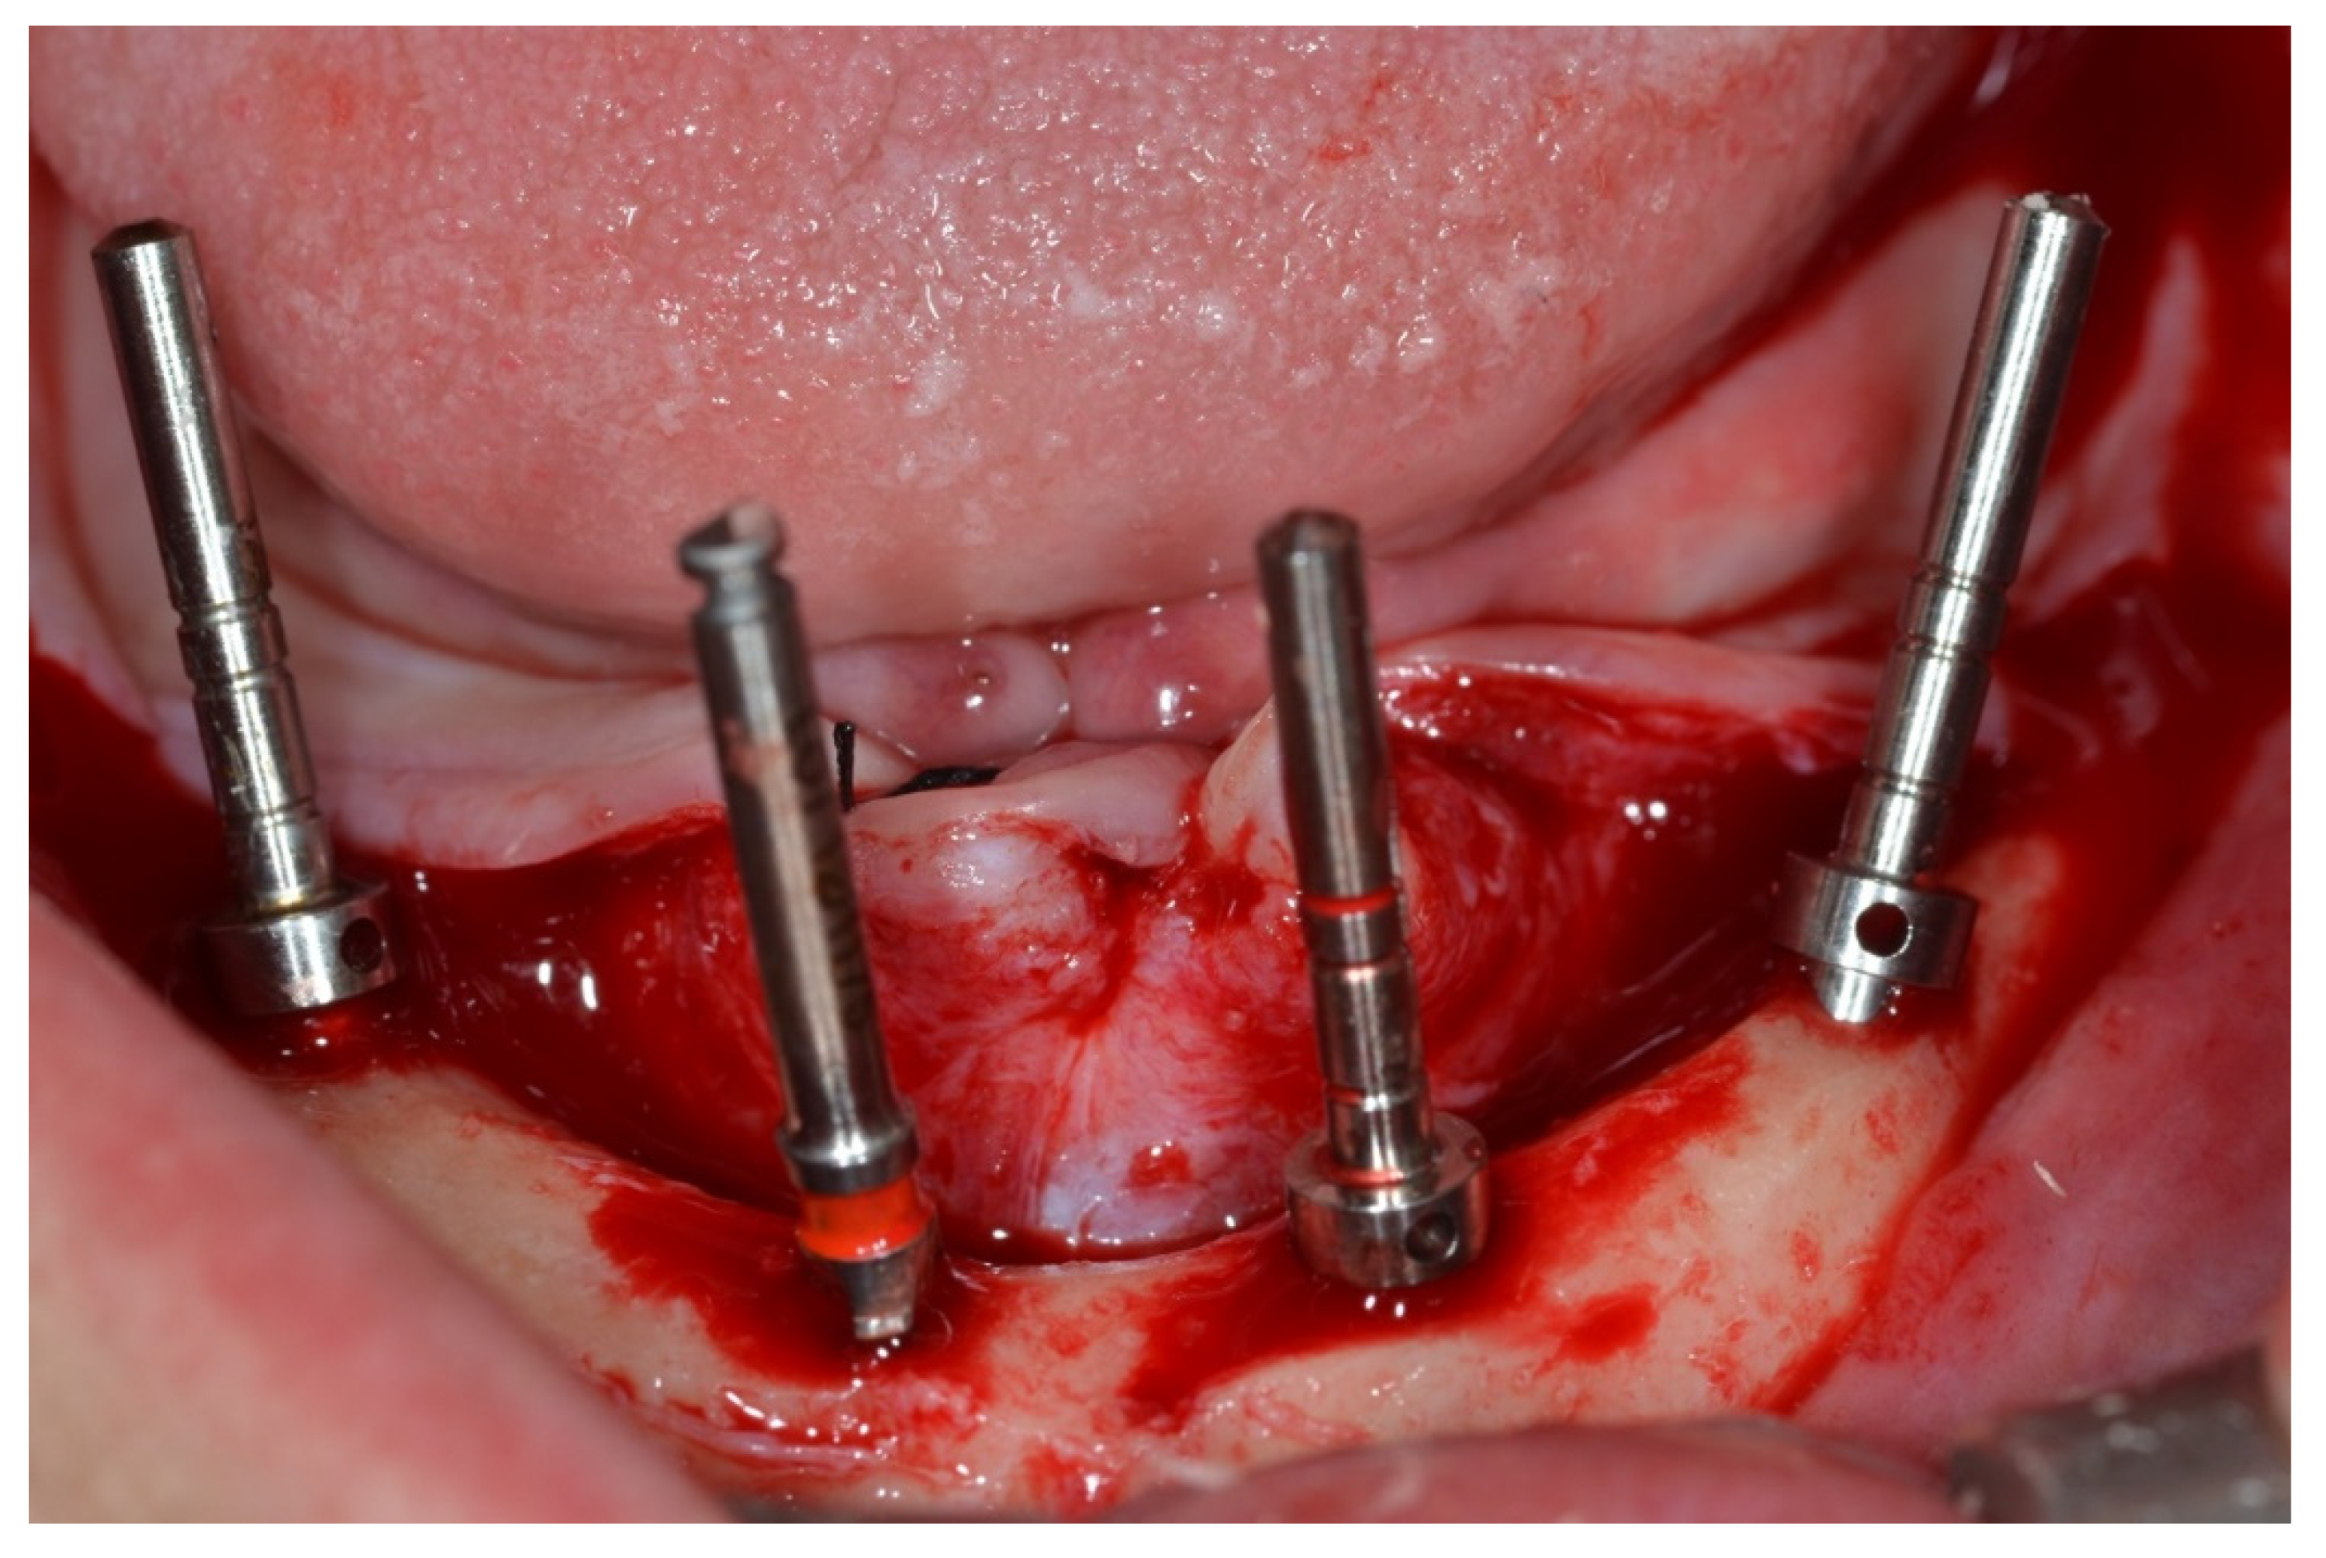

Surgical Protocol